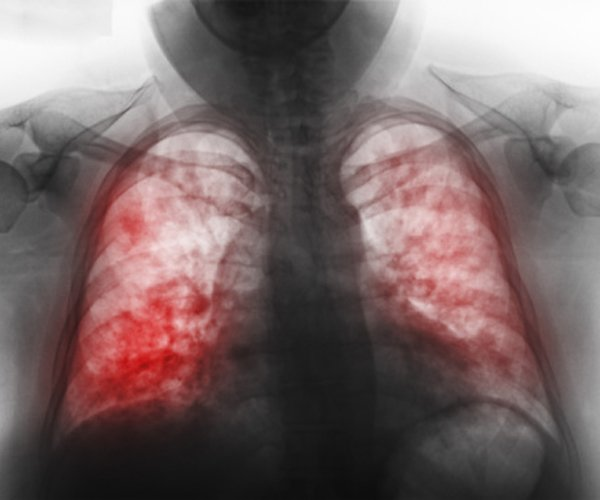

Давайте вспомним самые страшные эпидемии последних лет

Растущая эпидемия ранее неизвестного коронавируса пугает миллионы людей по всей планете. Настолько ли страшна пневмония нового типа? Встречались ли люди XXI века с более страшными массовыми инфекционными заболеваниями? Сейчас вспомним!

2002: Атипичная пневмония

В конце 2020 года на юге Китая, в провинции Гуандун, вспыхнула эпидемия SARS, тяжелого респираторного синдрома атипичной пневмонии. Инфекция распространилась не только на Китай и соседствующие азиатские страны, но и на Европу, Северную Америку и Новую Зеландию. В разгар эпидемии было выявлено 8437 случаев заражения, 813 из которых закончились летальным исходом.